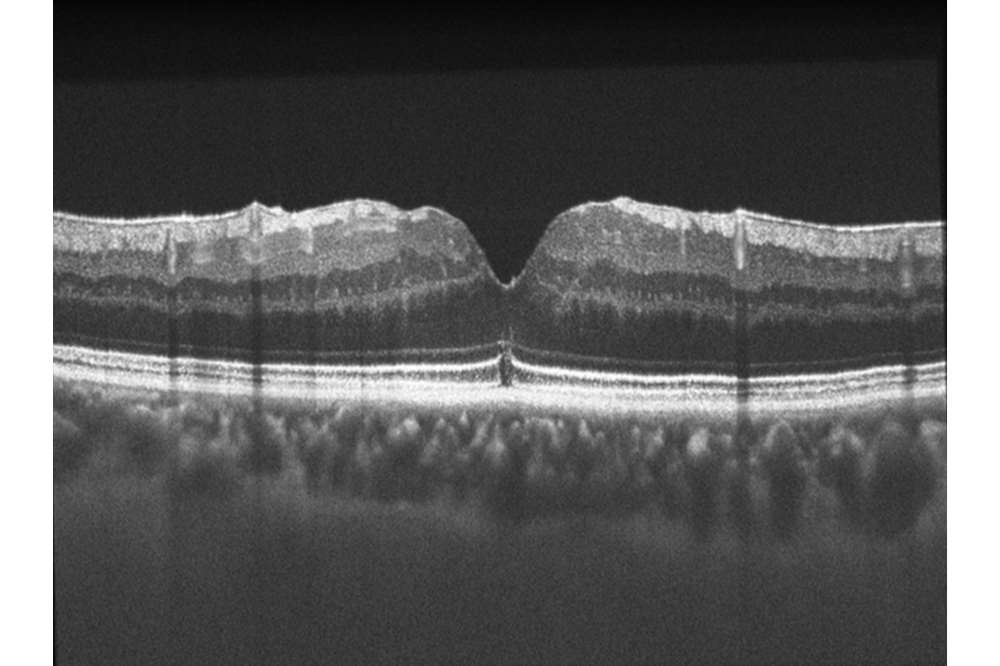

Postoperative Macular Hole

OCT B-scan from a patient 9 months following successful macular hole surgery.